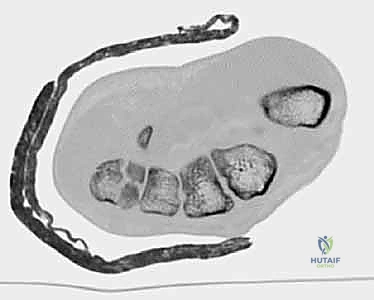

- الأشعة المقطعية (CT Scan): في الحالات المعقدة حيث يكون الكسر مفتتاً أو الخلع متعدداً، يطلب الدكتور أشعة مقطعية ثلاثية الأبعاد (3D CT). هذه التقنية توفر خريطة دقيقة جداً لحجم الشظايا العظمية وتساعد في التخطيط الجراحي بدقة متناهية.